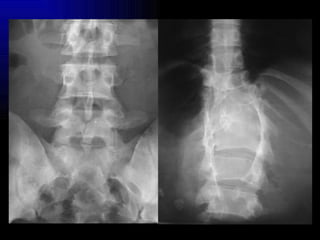

Escoliosis

Medición escoliosis con método de Cobb